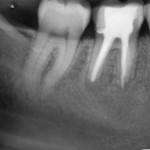

Bei klinischer Beschwerdefreiheit, zeigte sich bereits im August 2008 eine vollständige knochendichte Ausheilung des Defektes.

An diesem Fall kann man sehr gut erkennen, dass die apikale Parodontitis entsprechend einer Infektionskrankheit nach Abtöten der ursächlichen Keime vollständig ausheilt. Durch Behandlung nach dem „Goldstandard“ konnten anscheinend nicht alle Bakterien abgetötet werden, so dass ein Rezidiv unumgänglich war. Auch durch die folgende WSR konnte keine endgültige Heilung erzielt werden. Erst die Revision und gründliche Desinfektion mit CHKM führte zu einer knochendichten Ausheilung der apikalen Ostitis.

Interessant erscheint mir, dass die prognostisch günstigere Diagnose bei der Erstbehandlung (irreversible Pulpitis) im Vergleich zur ungünstigen Ausgangssituation bei der Folgebehandlung (Rezidiv nach WSR, Revisionsbehandlung) anscheinend keinen entscheidenden Einfluss auf den Therapieerfolg hat. Viel wichtiger ist die Anwendung eines indikationsgerechten Therapieprotokolls, welches alle Keime abtötet und somit eine Heilung ermöglicht.